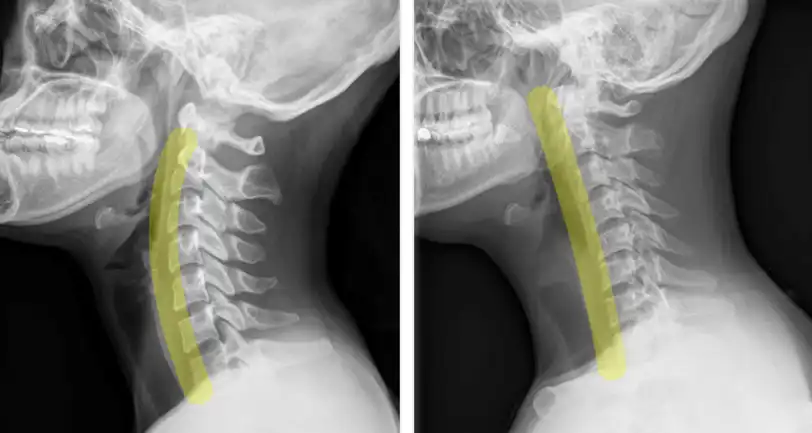

거북목은 허리와 등 위쪽, 그리고 목이 앞으로 구부러지면서 머리가 앞으로 내밀어진 상태를 말합니다.

거북목 또한 경추 전만이 없어져 일자목이 되고 앞으로 내민 머리를 치켜들기 위해 목덜미 쪽 근육에 과도한 힘이 들어가며 목 디스크에 걸리는 압박이 커지게 됩니다.

머리와 목이 정상 자세일 때는 목 디스크에 걸리는 무게가 5kg 정도인데 목을 앞으로 30도만 구부리면 목 디스크에 걸리는 무게가 무려 18kg가 넘게 됩니다. 이런 강한 압박을 오랜 시간 지속하게 되면 디스크를 찢고 찌그러뜨리게 되는데요.

이것은 목 디스크의 손상의 큰 원인이 됩니다.